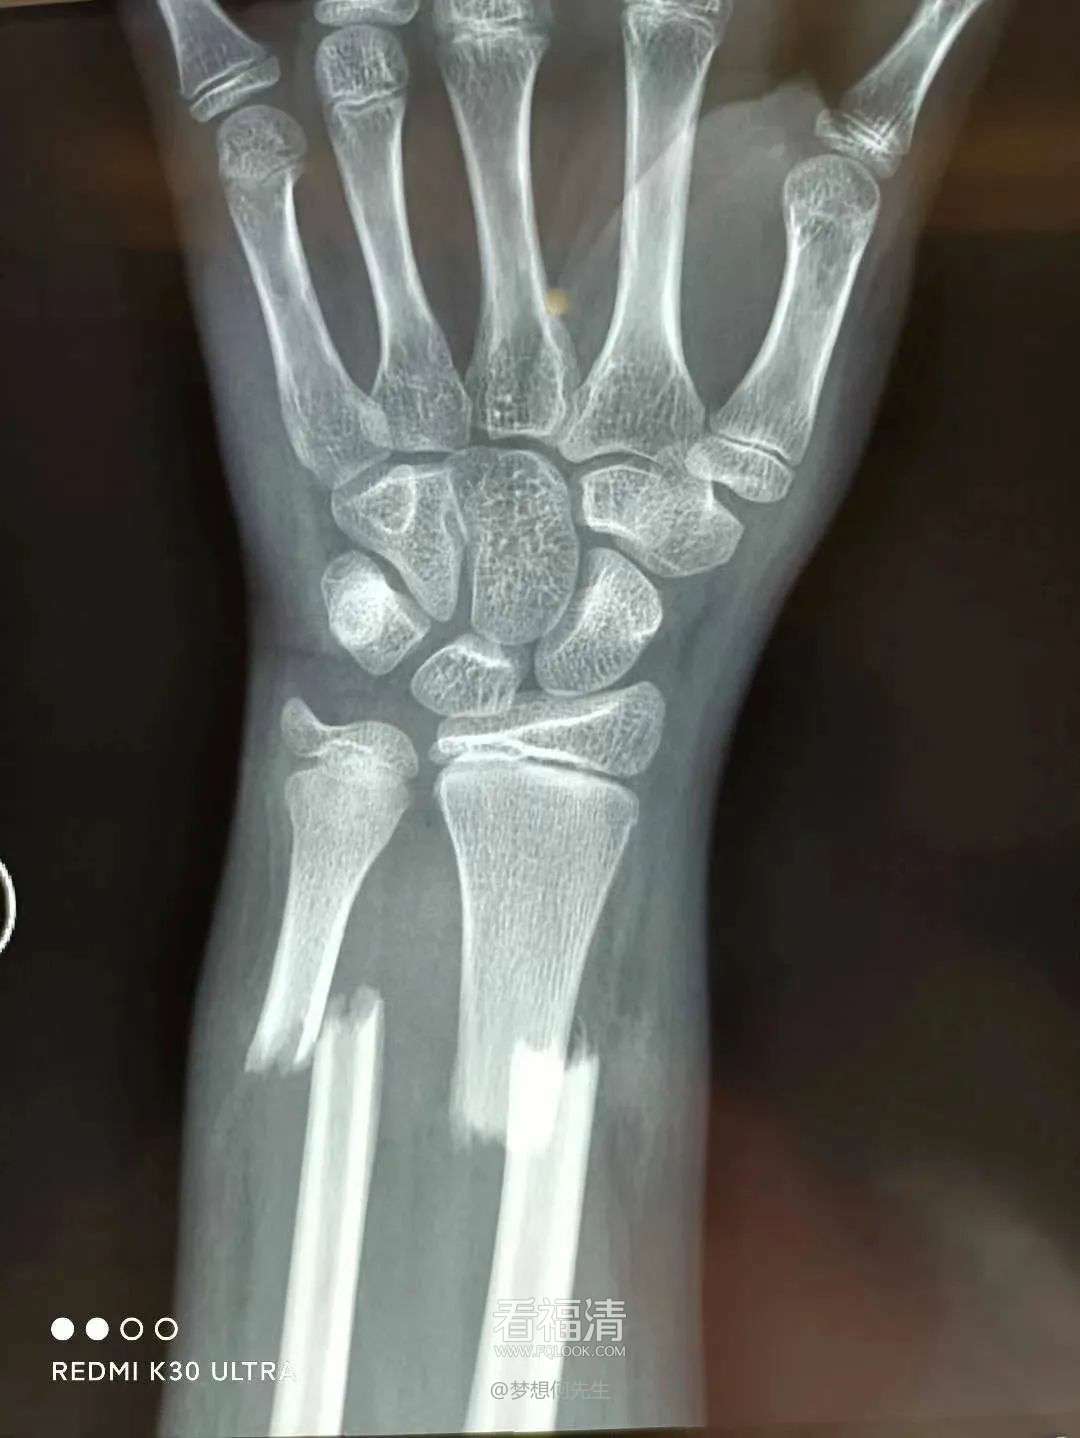

患者39岁,因外伤导致左手疼痛难忍,前来福清市第五医院中医骨科门诊寻求治疗。经过详细检查,患者被确诊为左侧桡骨远端粉碎性骨折伴下尺桡关节脱位。接诊的王征勇运用精湛的正骨手法进行复位,并在中医正骨理论的指导下,使用石膏进行固定。这种治疗方案有效地稳定了复位后的桡骨远端骨折,促进了骨折的愈合,避免了不必要的手术治疗,同时显著减轻了患者的疼痛感。

复位前

复位后